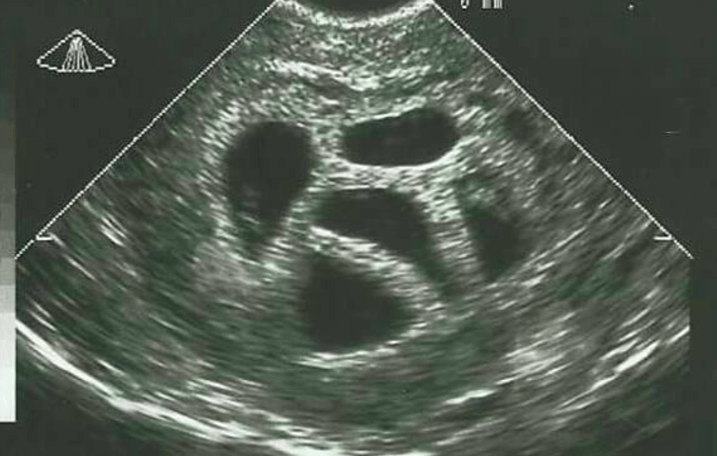

Er is een opmerkelijk verhaal te delen over een moeder genaamd Susan, die twintig jaar geleden voor een lastige beslissing stond. Op haar 28ste ontdekte ze dat ze in verwachting was van een vijfling. De artsen die haar bijstonden, raadden haar aan om te kiezen voor ‘selectieve abortus’. Dit houdt in dat je één of meer embryo’s kunt laten weghalen om de overlevingskansen van de andere te vergroten. Susan kon hier niet mee instemmen en besloot het advies naast zich neer te leggen.